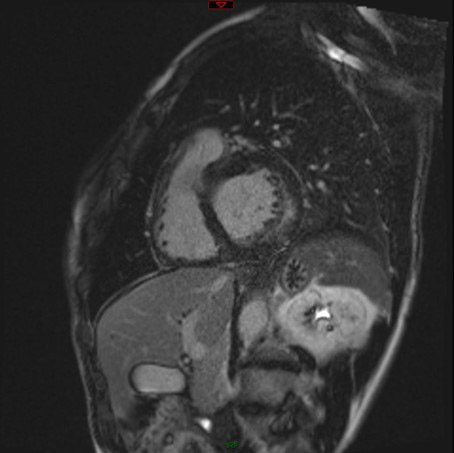

Une échographie cardiaque est demandée dans le bilan étiologique et devant l’aspect ECG (Vidéos 1 et 2, et Figure 2):

Vidéo 3 - Séquence Ciné-IRM coupe 4 cavités

Résultats de l’IRM cardiaque:

- Fonctions systoliques bi-ventriculaires conservées avec dilatation tétra-cavitaire

- HVG concentrique (masse VG à 128 g/m2 pour une normale < 90 g/m2) avec épaisseur maximale à 15 mm en antéro-septo-basal (Figure 7)

- Hypertrophie VD avec épaisseur diastolique à 5 mm (Figure 8)

- Hypertrophie des piliers mitraux (Figure 9) et trabéculations bi-ventriculaires

Figures 7, 8 et 9 (de gauche à droite)